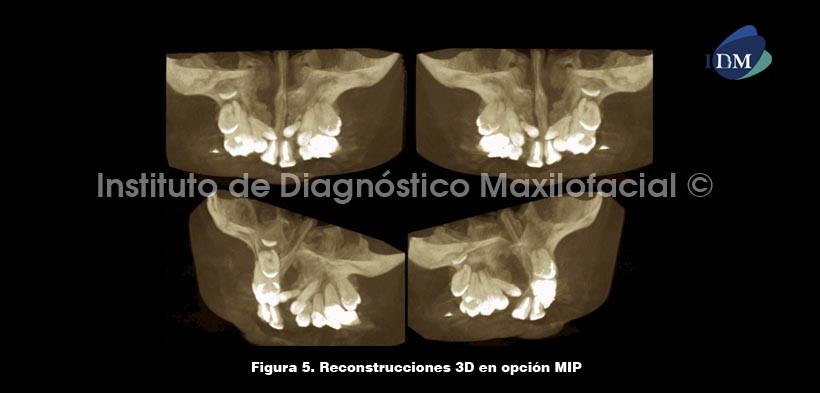

Así mismo, el software Romexis nos brinda diferentes opciones de reconstrucción 3D, como por ejemplo la opción radiográfico matizado que nos muestra preponderantemente las estructuras con alto contenido mineral como el tejido óseo. También tenemos la opción MIP, que nos ilustra la relación de los tejidos duros con la superficie facial del paciente. Finalmente, la opción radiográfico que nos ilustra la zona de estudio en escala de grises, la cual complementa de manera ideal las opciones anteriormente descritas (Fig. 5 y 6).